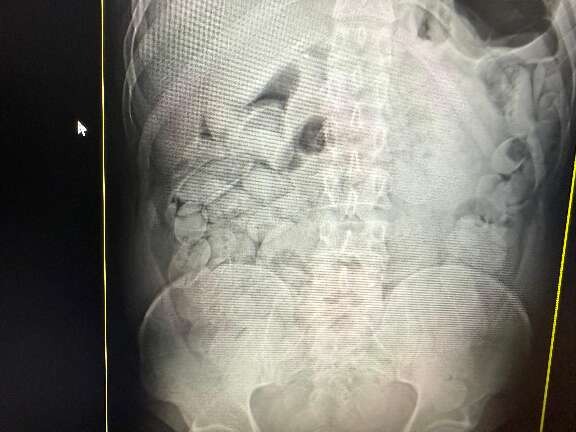

Na operação de quarta-feira, dos 18 presos, 17 haviam engolido cápsulas de droga. Cada um ingeriu aproximadamente 100 cápsulas, totalizando cerca de 1,1 quilo por pessoa. Os 17 bolivianos, 14 homens e três mulheres, permanecerão sob custódia da Receita Federal no Pronto-Socorro Municipal por um período de um a três dias, até a completa eliminação das cápsulas. Após o procedimento, todos serão encaminhados à Polícia Federal para as providências legais.